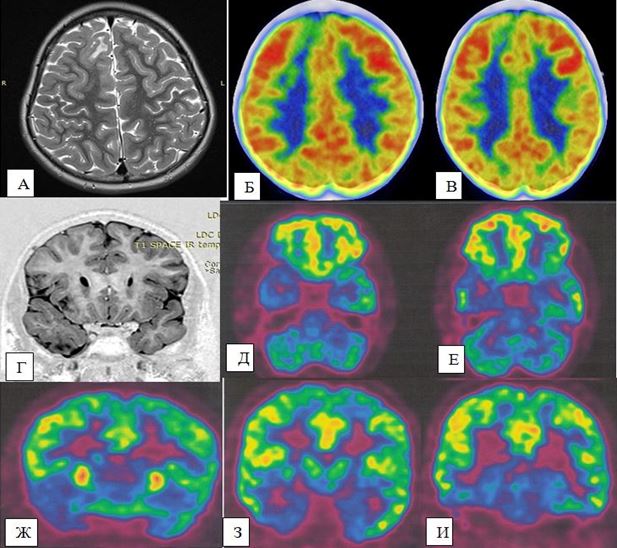

Результаты. По данным магнитно-резонансной томографии у 223 (93,3%) пациентов выявлены те или иные структурные изменения головного мозга. Рубцово-глиозно-кистозные и атрофические изменения обнаружены у 47 (21,1%), мальформации коркового развития - у 33 (14,8%), доброкачественные опухоли головного мозга - у 43 (19,3%), сосудистые мальформации - у 47 (21,1%), арахоидальные кисты - у 21 (9,4%), гиппокампальный склероз – у 12 (5,4%), факоматозы – у 11 (4,9%), энцефалит Расмуссена – у 5 (2,2%) и гамартомы гипоталамуса – у 4 (1,8%). На основании результатов позитронно-эмиссионной томографии выявлены участки гипометаболизма серого вещества головного мозга, соответствующие зонам метаболического дефицита вокруг эпилептического очага. Хорошие результаты хирургического лечения в отдаленном периоде - класс Engel I достигнут у 67,6%. Самые лучшие результаты (Engel I) отмечались после лезионэктомии (81,9%), темпоральных резекций (78,4%) и гемисферэктомии (72,7%).